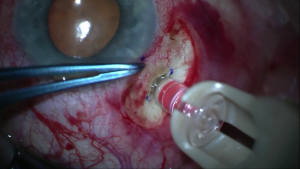

Video summarizing the major steps of the surgical implantation of the PDS, including peritomy, scleral dissection, pars plana laser ablation, pars plana incision, implant insertion, and closure of the conjunctiva and Tenon's capsule.

Insertion of the Susvimo implant involves exposure and dissection of the sclera, allowing for insertion of the device into the vitreous, followed by careful closure to avoid post-surgical complications. the procedure can be summarized in seven major steps as follows.[16]

- Preparation: Prepare the patient with induction of local anesthesia, standard surgical sterile procedures, dilation of the pupil, placement of a speculum, and insertion of an infusion line, ideally in the inferotemporal quadrant.

- Peritomy: After identifying the device insertion site 4 mm posterior to the limbus in the superotemporal quadrant, placing a traction suture is recommended to improve exposure for the remainder of the procedure. Perform a 6 mm by 6 mm limbal peritomy of both the conjunctiva and Tenon’s capsule with nontoothed forceps to preserve tissue integrity and allow for a bilayer closure. Generous blunt dissection is optimal to allow for adequate tissue coverage of the flange with minimal tension following implantation. Hemostasis is particularly important in this step and in stages 4, 5, and 6.

- Implant preparation: Draw the ranibizumab into the syringe using the filter needle, then switch to the fill needle and remove any air bubbles. Using the included insertion tool carrier, advance the syringe needle through the septum of the implant. Under the microscope, fill the implant slowly, over 5-10 seconds, to avoid injection of air into the body reservoir. When the implant is full as evidenced by a dome of fluid at the tip of the release control element, remove the syringe from the insertion tool carrier and replace it with the insertion tool handle.

- Scleral dissection: After ensuring the scleral surface is dry, use an MVR blade to dissect through the sclera to the pars plana at the insertion site, creating an incision precisely 3.5mm wide with squared edges to avoid tearing of tissue during device insertion. Incisions greater than 3.5 mm must be corrected by suturing wound edges before implantation.

- Pars plana laser ablation: Ablate the visible choroid in all exposed pars plana tissue with a 532 nm laser to prevent bleeding during implantation, paying close attention to the corners. Laser should start at 300 mW and 1000 ms and be applied as contiguous, overlapping single spots, but not painting strokes. As many as 70-100 laser spots may be executed before observing the desired endpoints of graying color, perforated appearance, and/or vitreous seeping through the pars plana. As this procedure may enlarge the incision, confirm the incision length of precisely 3.5 mm after this step before proceeding.

- Pars plana incision: Open the pars plana by passing a 3.2 mm slit knife through the center of the scleral incision, taking care to avoid lateral movements which may enlarge the incision or induce bleeding. Prolapse of vitreous during this step or the following step may be cleaned using a vitrector at the surgeon’s discretion; do not use other instruments such as sponges to avoid vitreous traction.

- Implant insertion: Remove the insertion tool handle loaded with the implant from the insertion tool carrier, being sure not to touch the implant to any surface to avoid placing an intraoacular foreign body. Stabilize the globe and use the insertion tool handle to insert the implant into the insertion site perpendicularly, aligning the long axis of the flange with the wound. A twisting motion may be used to pass the device through the incision, and the infusion line can be activated for counter pressure. Continue pushing the implant into the globe until the gripper tips that grasp the device press firmly against the sclera.

- Conjunctival and Tenon’s closure: Close both layers over the implant using interrupted 8-0 or 7-0 Vicryl or gut sutures, ensuring scleral bites at the limbus such that both layers overlap the peripheral cornea. Remove infusion cannula and traction suture, correcting any persistent leaks with suture as needed. Finally, check IOP digitally and implant placement with indirect ophthalmoscopy to confirm proper positioning.